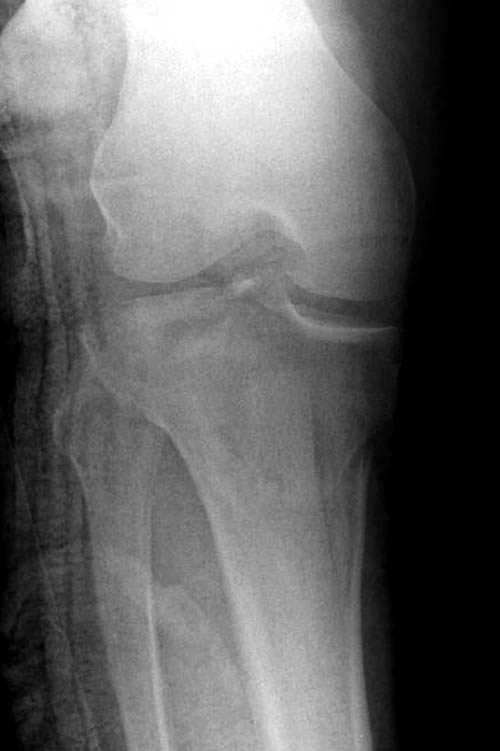

Перелом Schatzker VI является результатом высокой энергии, и здесь кроме мыщелков вовлечен диафиз и мягкие ткани. В данный момент мероприятия по улучшении состояния кожного покрова и мягких тканей можно разобрать вопросы остеосинтеза.

Еще одно дополнение, некоторые в прочтении перелома медиального мыщелка делают типичные ошибки, например, редко переломы медиального мыщелка бывают “только медиальными”, а часто с наличием сложного, заднего компонента, который часто смещается кзади.

На боковом рентгене, явный задний смещенный компонент. КТ поможет увидеть "вершину" перелома, куда надо поставить антискользящую пластину из заднего или задне-медиальнего доступа. Для стабилизации боковой колонны традиционный боковой доступ через Girdle tubercle с длинной блокирующей пластиной. Одна задняя подпорка не удержит медиальную колонну, требуется длинная медиальная пластина.